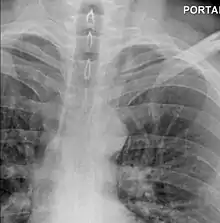

Upright chest radiography showing mediastinal air adjacent to the aorta and tracking cephalad adjacent to the left common carotid artery. This patient presented to the emergency department with severe chest pain after eating.

The diagnosis of Boerhaave's syndrome is suggested on the plain chest radiography and confirmed by chest CT scan. The initial plain chest radiograph is almost always abnormal in patients with Boerhaave's syndrome and usually reveals mediastinal or free peritoneal air as the initial radiologic manifestation. With cervical esophageal perforations, plain films of the neck show air in the soft tissues of the prevertebral space.

Hours to days later, pleural effusion(s) with or without pneumothorax, widened mediastinum, and subcutaneous emphysema is typically seen. CT scan may show esophageal wall edema and thickening, extraesophageal air, periesophageal fluid with or without gas bubbles, mediastinal widening, and air and fluid in the pleural spaces, retroperitoneum or lesser sac.